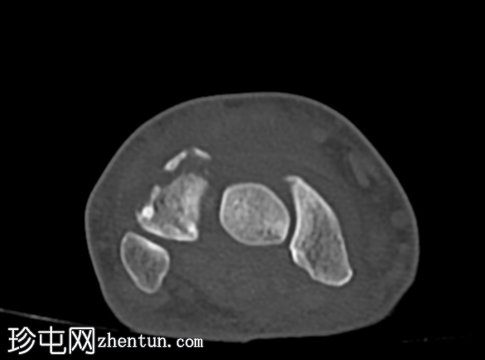

CT

轴位片

平扫

冠状位片

矢状位片

CT轴位、矢状位和冠状位片显示三角骨背侧粉碎性撕脱性骨折。

未见其他骨折。